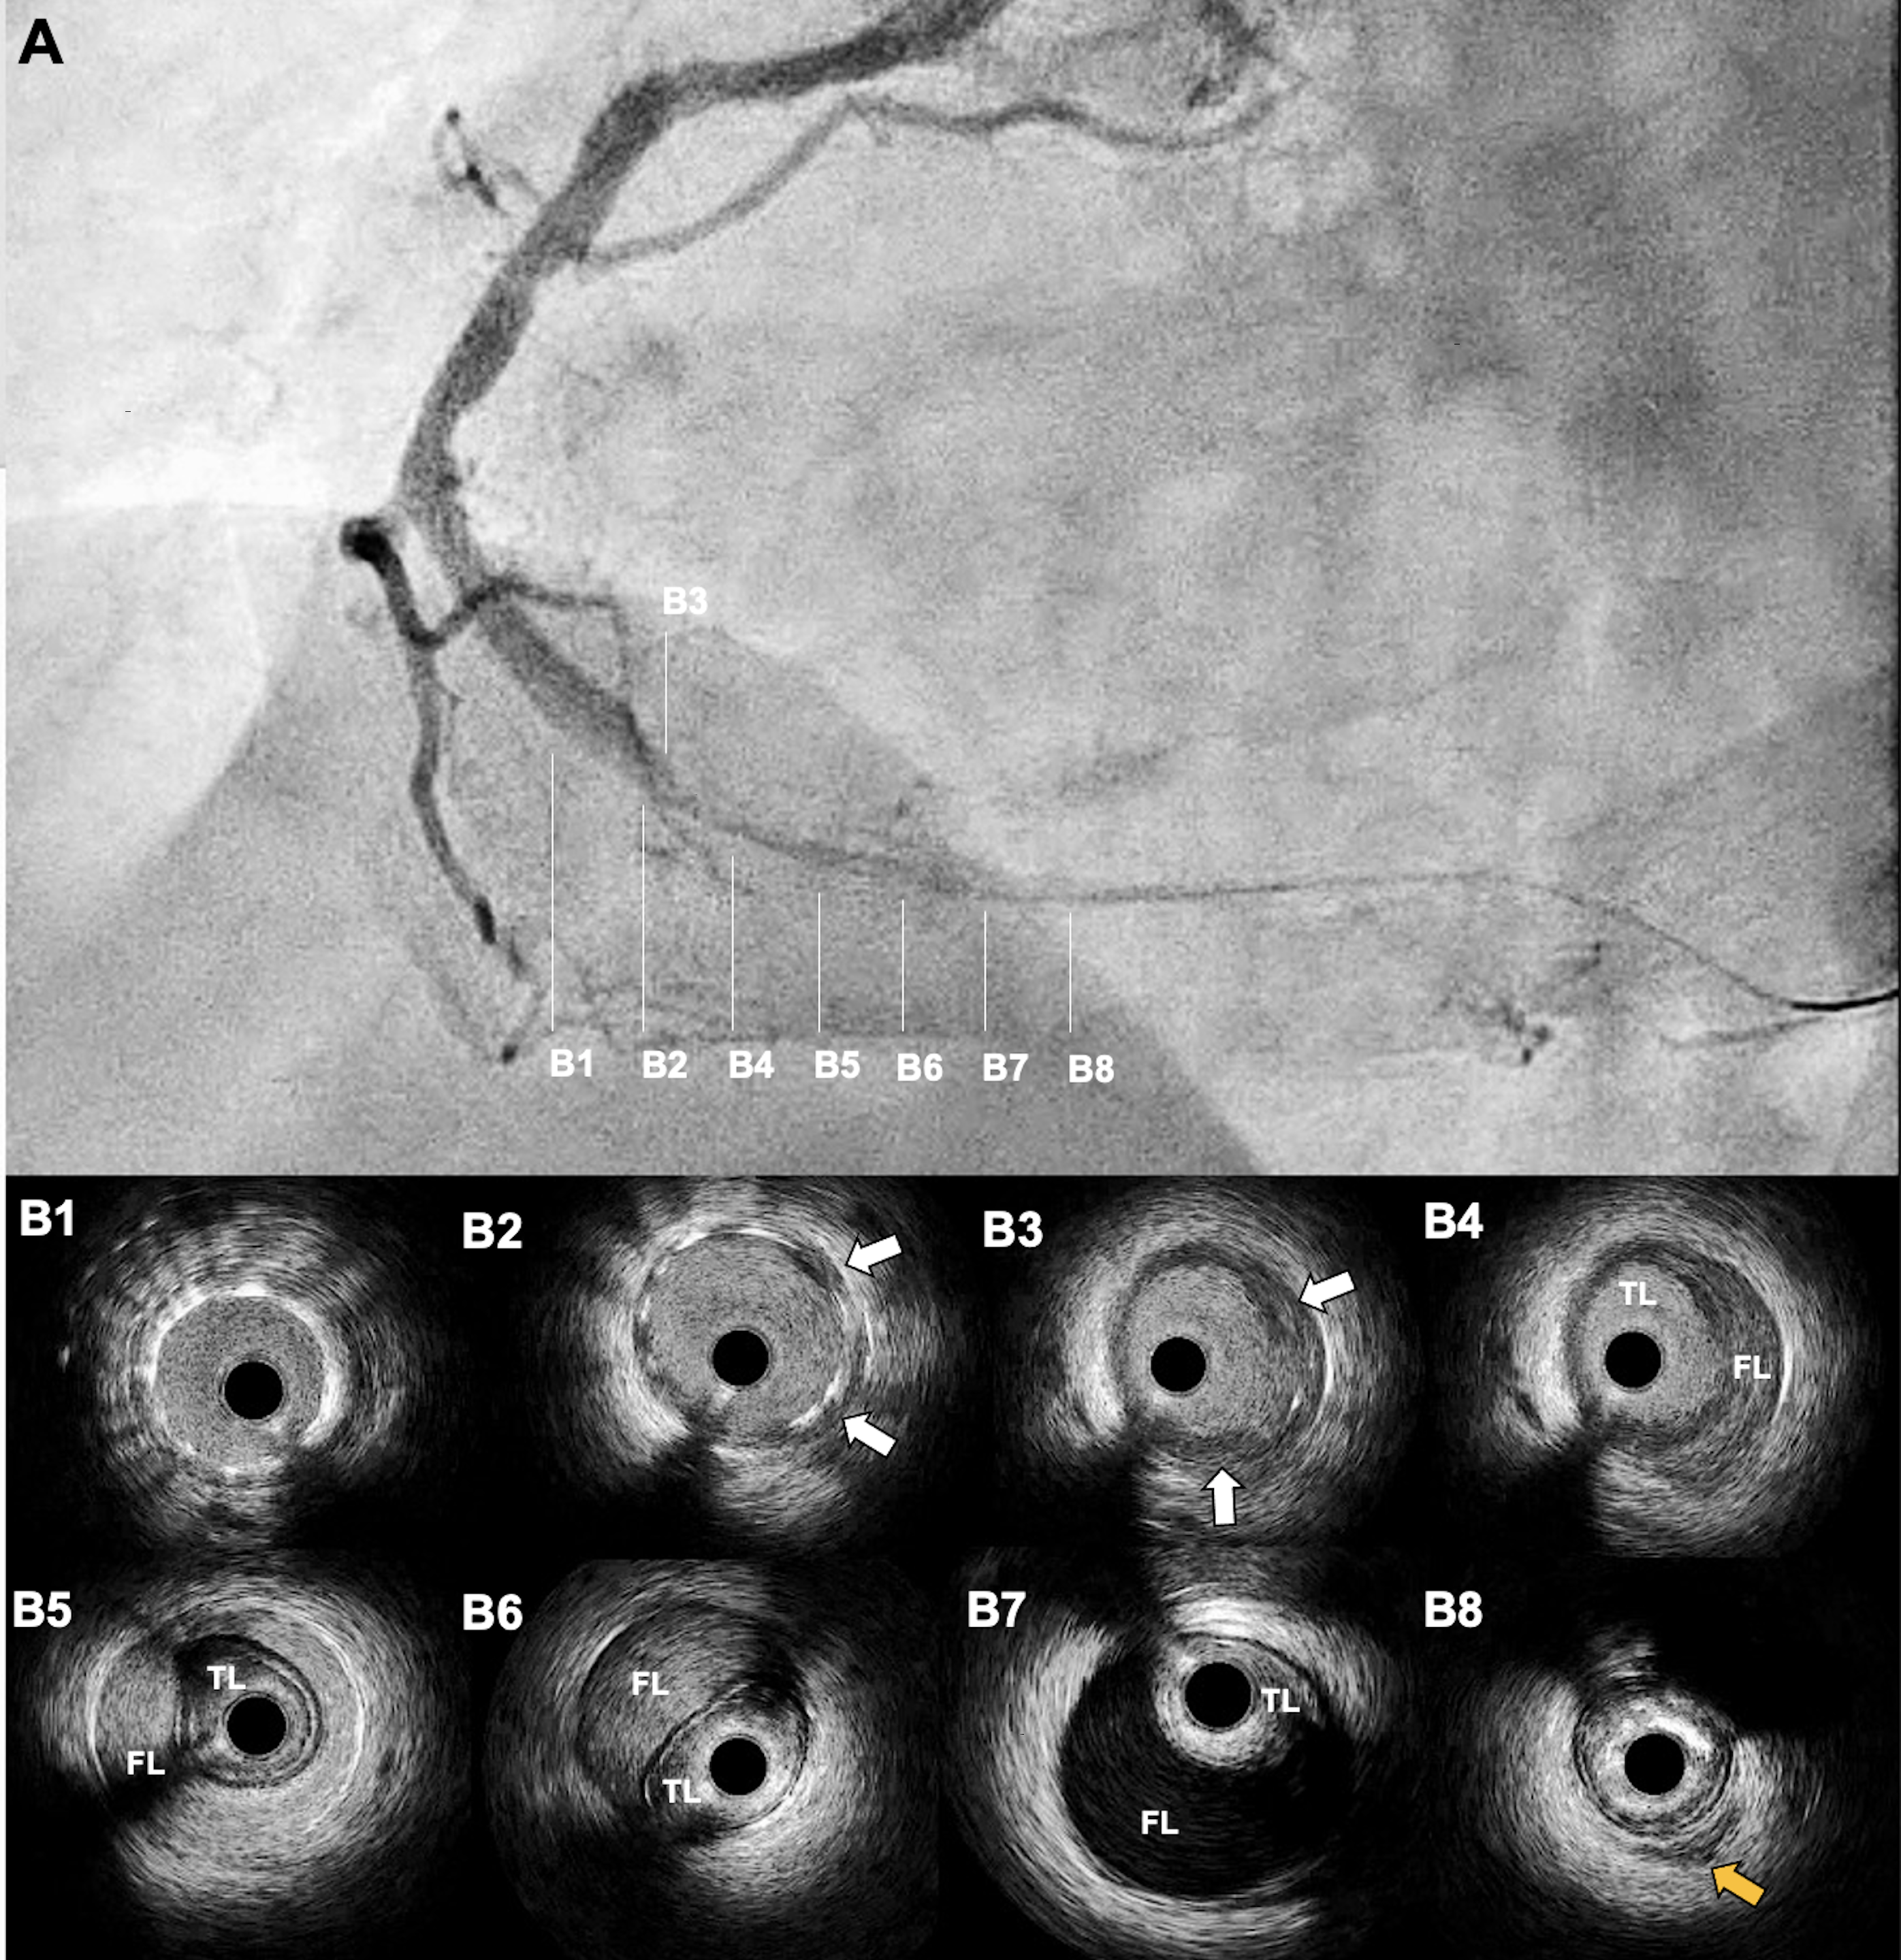

Two hours later, the patient developed recurrent chest pain with inferior ST-segment re-elevation. Repeat CAG revealed acute stent thrombosis (AST) (Figure 2A, Video 2). Thrombus aspiration was performed, and intravascular ultrasound (IVUS) showed a large diffuse intramural hematoma (IH) distal to the ZES, without underexpansion or malapposition (Figure 2B). The IH was fenestrated using a 3.5 x 6.0-mm cutting balloon (Figure 3A, Video 3). Repeat IVUS confirmed multiple fenestration tracts (Figure 3B, Video 4). Two additional overlapping ZES were successfully implanted (Figure 3C). The patient was discharged uneventfully after 48 hours and remained asymptomatic at the 1-month follow-up.

IH is a rare cause of AST that results from subintimal blood propagation beyond the stent edge, leading to luminal compression. Angiography often underestimates IH, which makes IVUS essential for diagnosis and procedural guidance. This case highlights the importance of intracoronary imaging, supports balloon fenestration for IH, and emphasizes it as a treatable but underrecognized complication.